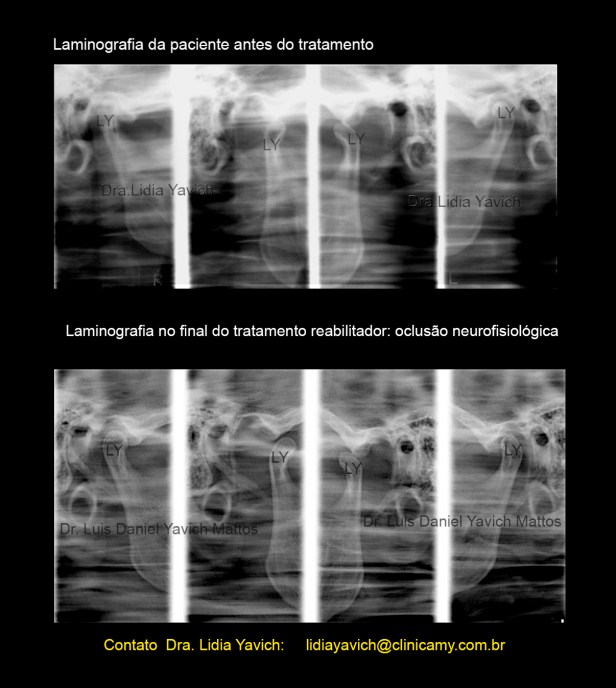

A Laminogafia da paciente em oclusão habitual mostra retroposição dos côndilos mandibulares e uma sequela de traumatismo na primeira infancia (no lado esquerdo).

Pode-se observar nesta imagem a alteração do eixo de crescimento do côndilo mandibular. Alterações na Orientação do Côndilo Mandibular Devido a Traumatismos na Primeira Infância

Laminografia mostrando a descompressão tridimensional das cabeças mandibulares.

Comparação das laminografias antes e após a reabilitação neuromuscular fisiológica combinada com e a ortodontia tridimensional